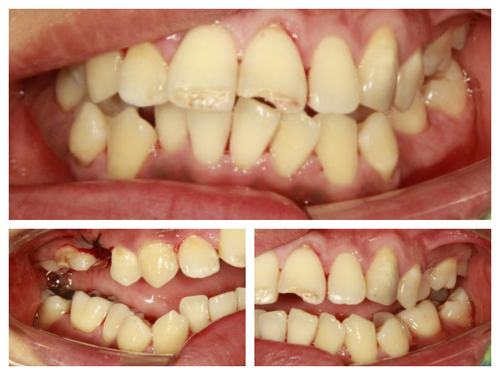

역시 스켈링도 못 받으셨던것 같다.. 약이 들어가고 주무시기 시작해서야 겨우 구강 상태를 살필 수 있었다..

발치가 필요한 치아, 심한 충치가 있는 치아, 치료가 마무리 되지 못한 치아..

첫 날 진료가 끝나고 환자와 다시 마주하고는 양치질 하시기도 힘드시겠네요.. 했더니 정말 그렇다며 오랜만에 스켈링 받아서 입이 개운한 것 같다신다.